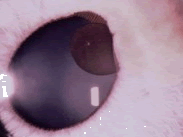

男性,79岁,双眼视物模糊4年余,裂隙灯检查如图,双眼还可能出现的症状有哪些()

-